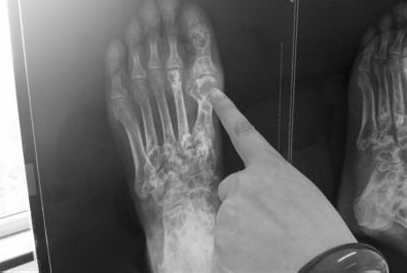

杜爱华医生替段先生做了详细的检查,由于段先生平时喜欢吃大鱼大肉,鲍参翅肚,体内尿酸浓度很高,通过X片显示,段先生的大脚趾关节形成多颗珍珠大的痛风石,情况不是很乐观。杜爱华医生建议进行“中医微创可视针刀镜技术”科学诊疗方案治疗。

(图:段先生的X光片显示,其左脚大拇指处痛风石较为严重)